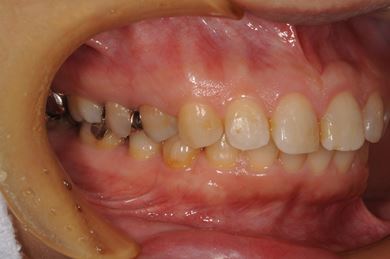

抜歯即日スピードインプラント治療+セラミック治療+歯肉歯槽骨整形術

| 治療方針 | 左下欠損部と保存不能の歯を抜歯し、インプラント治療にて機能的・審美的回復を行う。 | ||||||||||||||||||||||||||||||||

| 治療内容 | インプラント2本(抜歯即日スピードインプラント)、ハイブリッドセラミッククラウン2本、歯肉歯槽骨整形術 | ||||||||||||||||||||||||||||||||